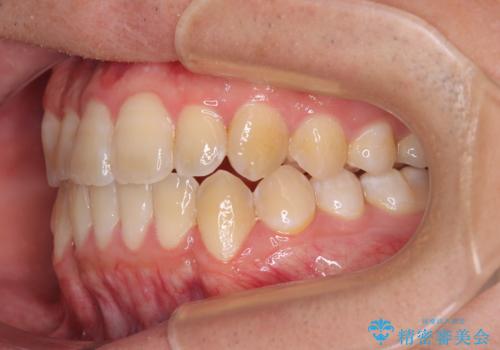

オープンバイトをインビザラインで矯正治療

- 前歯の開咬を気にして来院された患者様です。

開咬の治療は、前歯を閉じるように動かすとともに、上下臼歯を圧下(骨内にめり込ませる)させることで進めて行きます。

インビザラインは臼歯の圧下を効果的に行えるため、インビザラインを用いて矯正治療を行うこととしました。